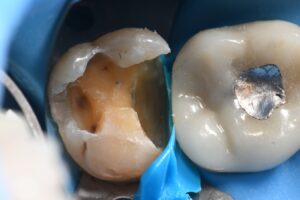

March 10, 2026 (Afternoon tea pics 2341.3: Kerr Simplishade | Rhondium DME | Garrison Dental Solutions – North America) Getting d o w n with DME. #RhondiumDME #KerrSimplishade #GarrisonCompositight Previous Post